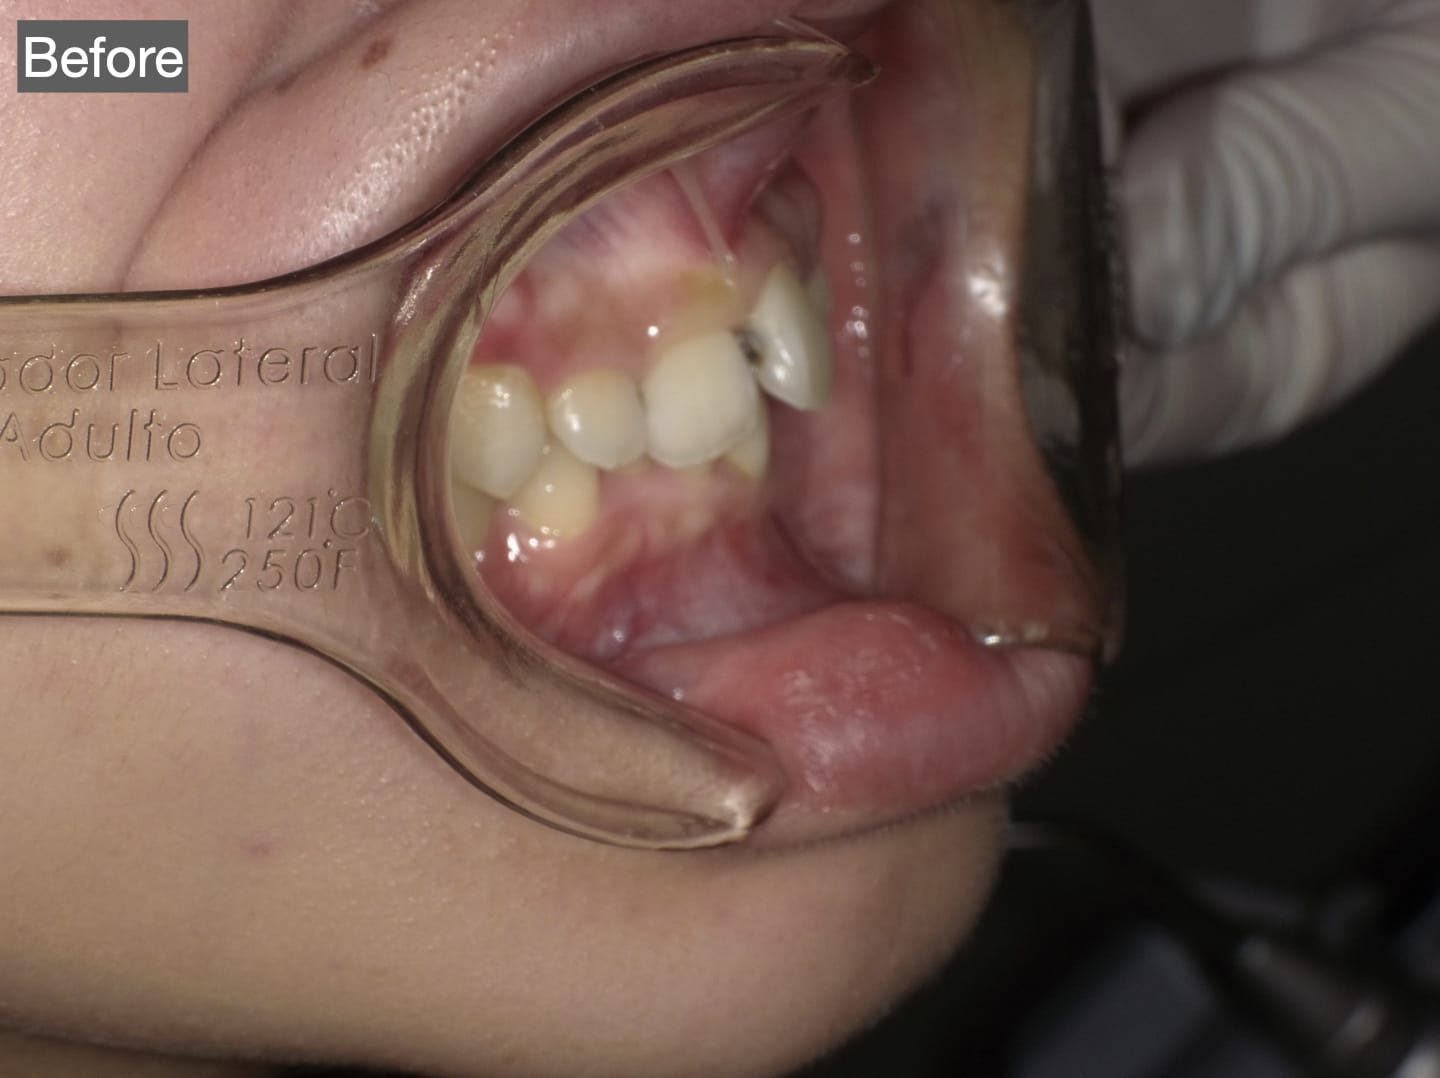

Case006

審美歯科の症例です。

【患者様の主訴】

・歯を小さくしながら、出っ歯を治したい。

・歯の色も白く、形も綺麗にしたい。

【治療方法・期間】

・ジルコニアセラミックによる審美歯科

・来院回数 3回

・治療期間 20日

・治療費:1,920,000円〜2,560,000円

患者様にはとても喜んで頂けて、歯科医として仕事をしてる私にとっても嬉しかったです。

担当:理事長 佐藤悠野

かぶせもの:ジルコニアセラミック

Before写真の上顎中央にあるような、大きく向きを変えなければならない歯がある場合、歯の神経を取る必要がある場合がある